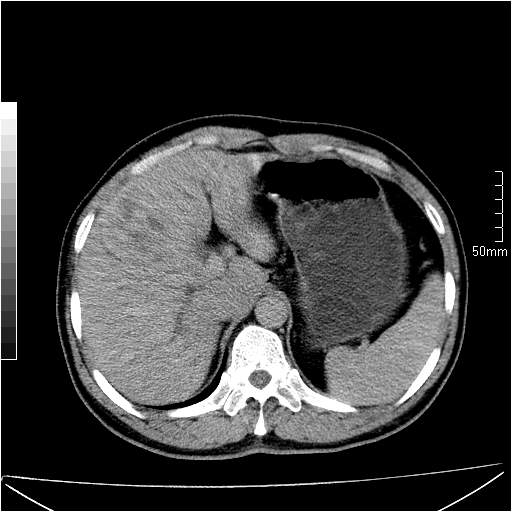

男性,54岁,皮肤黄染,搔痒一周余.b超示肝左叶回声异常.初步诊断1胆总管下段结石2胆囊结石伴慢性胆囊炎请各位战友帮忙看一下肝脏多发低密度如何解释恰当.增强效果不是很好.请大家见谅.

胆总管及肝内胆管扩张,考虑是结石!但,肝内的低密度区增强不明,可能是肝ca,因为肝ca在增强时呈快进快出.另年胆总管扩张原因,可以考虑一下是不是,胆管ca.再次要考虑肝内的低密度是否为海绵状血管瘤所致!

首先,胆总管下端结石梗阻伴肝内胆管扩张可确定。

其次,增强动脉期肝静脉显影,肝实质密度不均。——此为右心功能不全引起肝淤血的表现。

另外,肝八段低密度占位,呈多灶性,考虑肝脓肿或肝癌可能,(图像质量欠佳)建议进一步检查。

由于胆囊窝内结构显示不清,肝脏病灶又邻近胆囊窝首先考虑胆囊癌肝受侵犯。而后因肝脏病灶强化有渐进改变,且相邻胆管扩张,故考虑肝胆管细胞癌待排。

左肝胆管细胞癌。

胆总管下端结石。